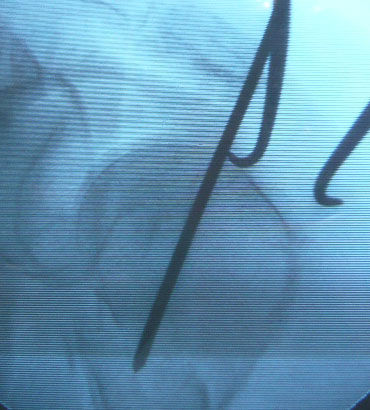

至適位置から髄内釘を挿入するためには、転位した上腕骨頭を整復する必要があります。私は2.4 K-wireを肩峰外側ぎりぎりから上腕骨頭に刺入して、これをjoy-stickにして整復しています。

K-wireは、大結節から刺入するよりも上腕骨頭の頂点から刺入する方が整復しやすいと思います。K-wireで上腕骨頭を内転位に保ちながら、至適位置からガイドワイヤーを挿入します。

K-wireで上腕骨頭を内転位に整復位を保っておかないと腱板に牽引されて外転転位してしまい、髄内釘のエントリーポイントがかなり大結節寄りになってしまいます。